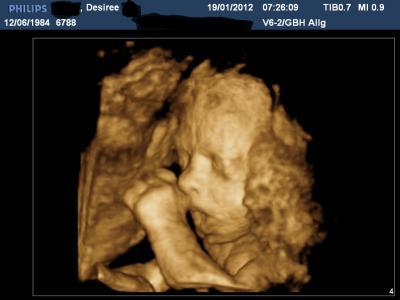

So kann jetzt auch endlich mal ein Ultraschall zeigen War heute beim Wunschultraschal mit DVD und süßen Filmchen von unserer Maus :-) ... Bin heute bei 27 + 4 und meine Maus wiegt jetzt 1160 gr. Vor 4 Wochen wog sie noch 632 gr GlG Desiree

Hallo Desiree, Oh ist das süüüß mit dem offenen Mündchen! Hat sich deine kleine Maus ja gut gemacht in den 4 Wochen! Liebe Grüße Sonja